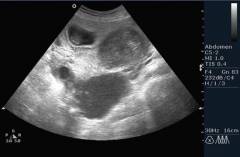

УЗИ малого таза является важным диагностическим инструментом при исследовании причин бесплодия. Врачи отмечают, что данное исследование позволяет оценить состояние органов репродуктивной системы, таких как яичники, матка и фаллопиевы трубы. Показаниями для проведения УЗИ могут служить нарушения менструального цикла, боли внизу живота, а также подозрения на наличие кист, миом или других патологий.

Процедура обычно проводится трансвагинально или трансабдоминально, что позволяет получить четкие изображения исследуемых органов. Врачи подчеркивают, что результаты УЗИ могут выявить аномалии, такие как полипы, миомы или кисты, а также оценить состояние фолликулов и эндометрия. Эти данные помогают в дальнейшем выборе методов лечения и повышают шансы на успешное зачатие.

УЗИ малого таза — важный диагностический метод при бесплодии, который позволяет выявить различные патологии. Основные показания для проведения исследования включают нарушения менструального цикла, боли внизу живота, а также подозрения на кисты или миомы. Во время процедуры исследуются яичники, матка и фаллопиевы трубы. УЗИ может быть выполнено трансабдоминально (через живот) или трансвагинально, что обеспечивает более детальное изображение органов.

Результаты УЗИ могут варьироваться: от нормального состояния органов до выявления аномалий, таких как поликистоз яичников или эндометриоз. Эти данные помогают врачам определить дальнейшую тактику лечения и выбрать оптимальные методы для достижения беременности. Многие женщины отмечают, что процедура безболезненная и информативная, что делает УЗИ важным этапом в диагностике бесплодия.

Ультразвуковое исследование органов малого таза — стандартный метод диагностики бесплодия благодаря своей доступности, безопасности и информативности. Обычно УЗИ назначает врач-гинеколог, но это может сделать и другой специалист по бесплодию. В некоторых городах есть специализированные центры репродуктологии, где медицинский персонал помогает в зачатии.

УЗИ выявляет только макроскопические изменения и не применяется при подозрении на функциональные расстройства. Однако изменения, видимые на УЗИ, могут указывать на нарушения менструальной функции, вызванные как структурными, так и функциональными проблемами.